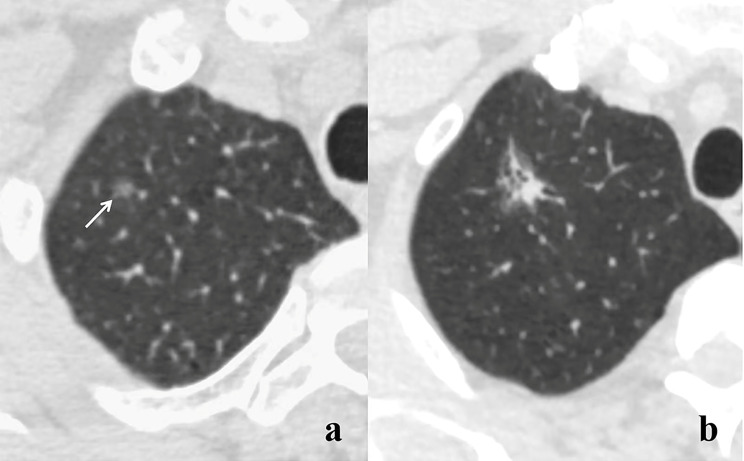

Background: Neoplastic ground glass nodules (GGNs) are relatively indolent tumors, with slow progression in invasiveness and computed tomography (CT) features. This study aimed to explore the correlation between pathological and CT characteristics and gene mutations in neoplastic GGNs.

Methods: We retrospectively analyzed 1,348 neoplastic GGNs from January 2019 to November 2022, including 290 adenocarcinomas in situ (AIS), 448 microinvasive adenocarcinomas (MIA), and 610 invasive adenocarcinomas (IAC). The correlations between patients' characteristics, pathological subtypes and grades, CT features, changes in follow-up, and gene mutations were analyzed.

Results: Solid component (odds ratio [OR] = 1.493; P = 0.014), larger size (OR = 1.049; P = 0.006), ill-defined boundary (OR = 1.368; P = 0.027), and lobulation sign (OR = 1.824; P = 0.001) were revealed as independent CT predictors of gene mutation. From AIS to IAC, the epidermal growth factor receptor (EGFR) mutation rate significantly increased (P < 0.01), while the kirsten rat sarcoma viral oncogene (KRAS) and the anaplastic lymphoma kinase (ALK) mutation rates significantly decreased (P < 0.05). Among IACs, mutation rate was the highest in the intermediate-grade ones (P < 0.05). Gene mutations were more frequently detected in nodules showing changes during follow-up (76.3% vs. 61.1%, P = 0.02), especially in those with more than 2-year follow-up (77.1% vs. 43.7%, P = 0.023). However, the specific changes were not associated with gene mutations (P = 0.273).

Conclusions: Gene mutations in neoplastic GGNs were associated with CT features, pathological subtypes and grades, and changes observed during long-term follow-up.